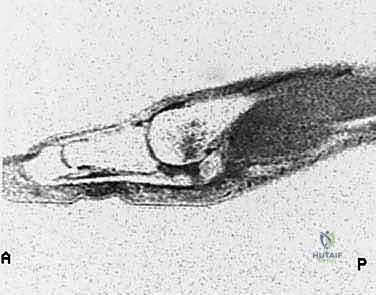

إصابة إصبع القدم العشبي (Turf Toe): دليل شامل للتشخيص والعلاج الجراحي مع الأستاذ الدكتور محمد هطيف

اكتشف كل ما يخص إصابة إصبع القدم العشبي (Turf Toe) من التشخيص الدقيق إلى خيارات العلاج الجراحي المتقدمة. تعرف على الأعراض، الأسباب، وكيف يم…